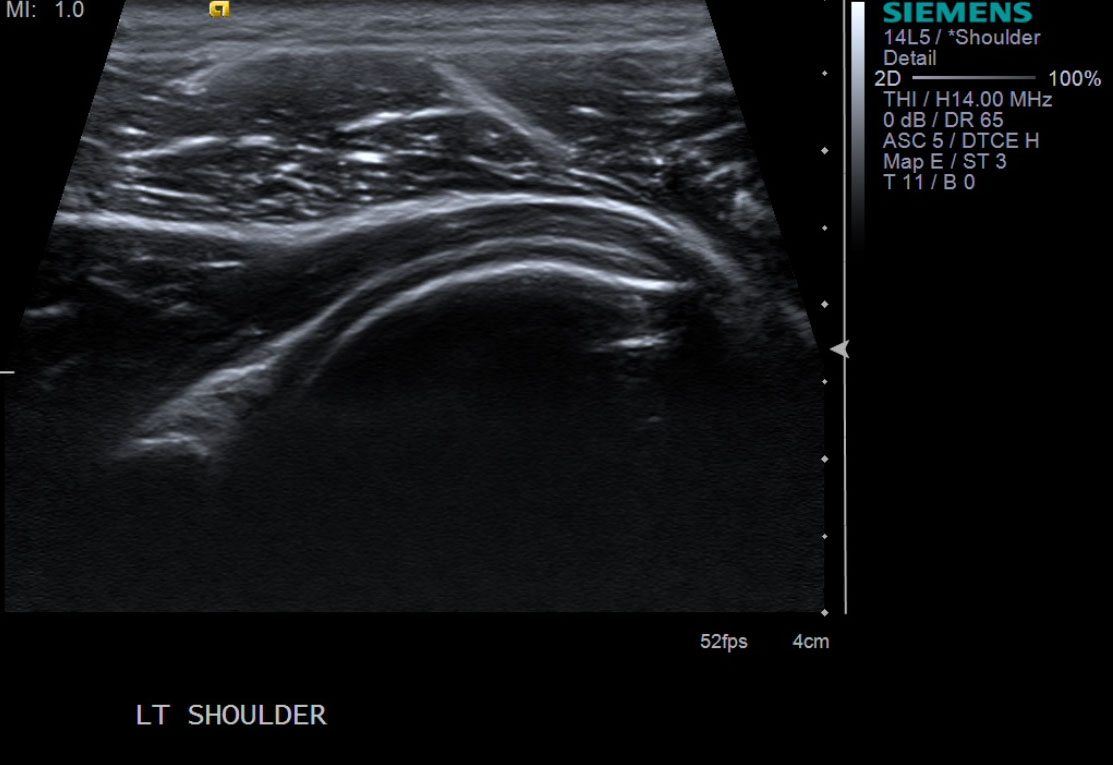

3. Scan patient looking for the posterior glenohumeral joint space. Image at the level of the infraspinatus tendon insertion in longitudinal orientation. Position probe so you can inject from anterior.

• descriptiondescription

• Mouse over image for annotated version.